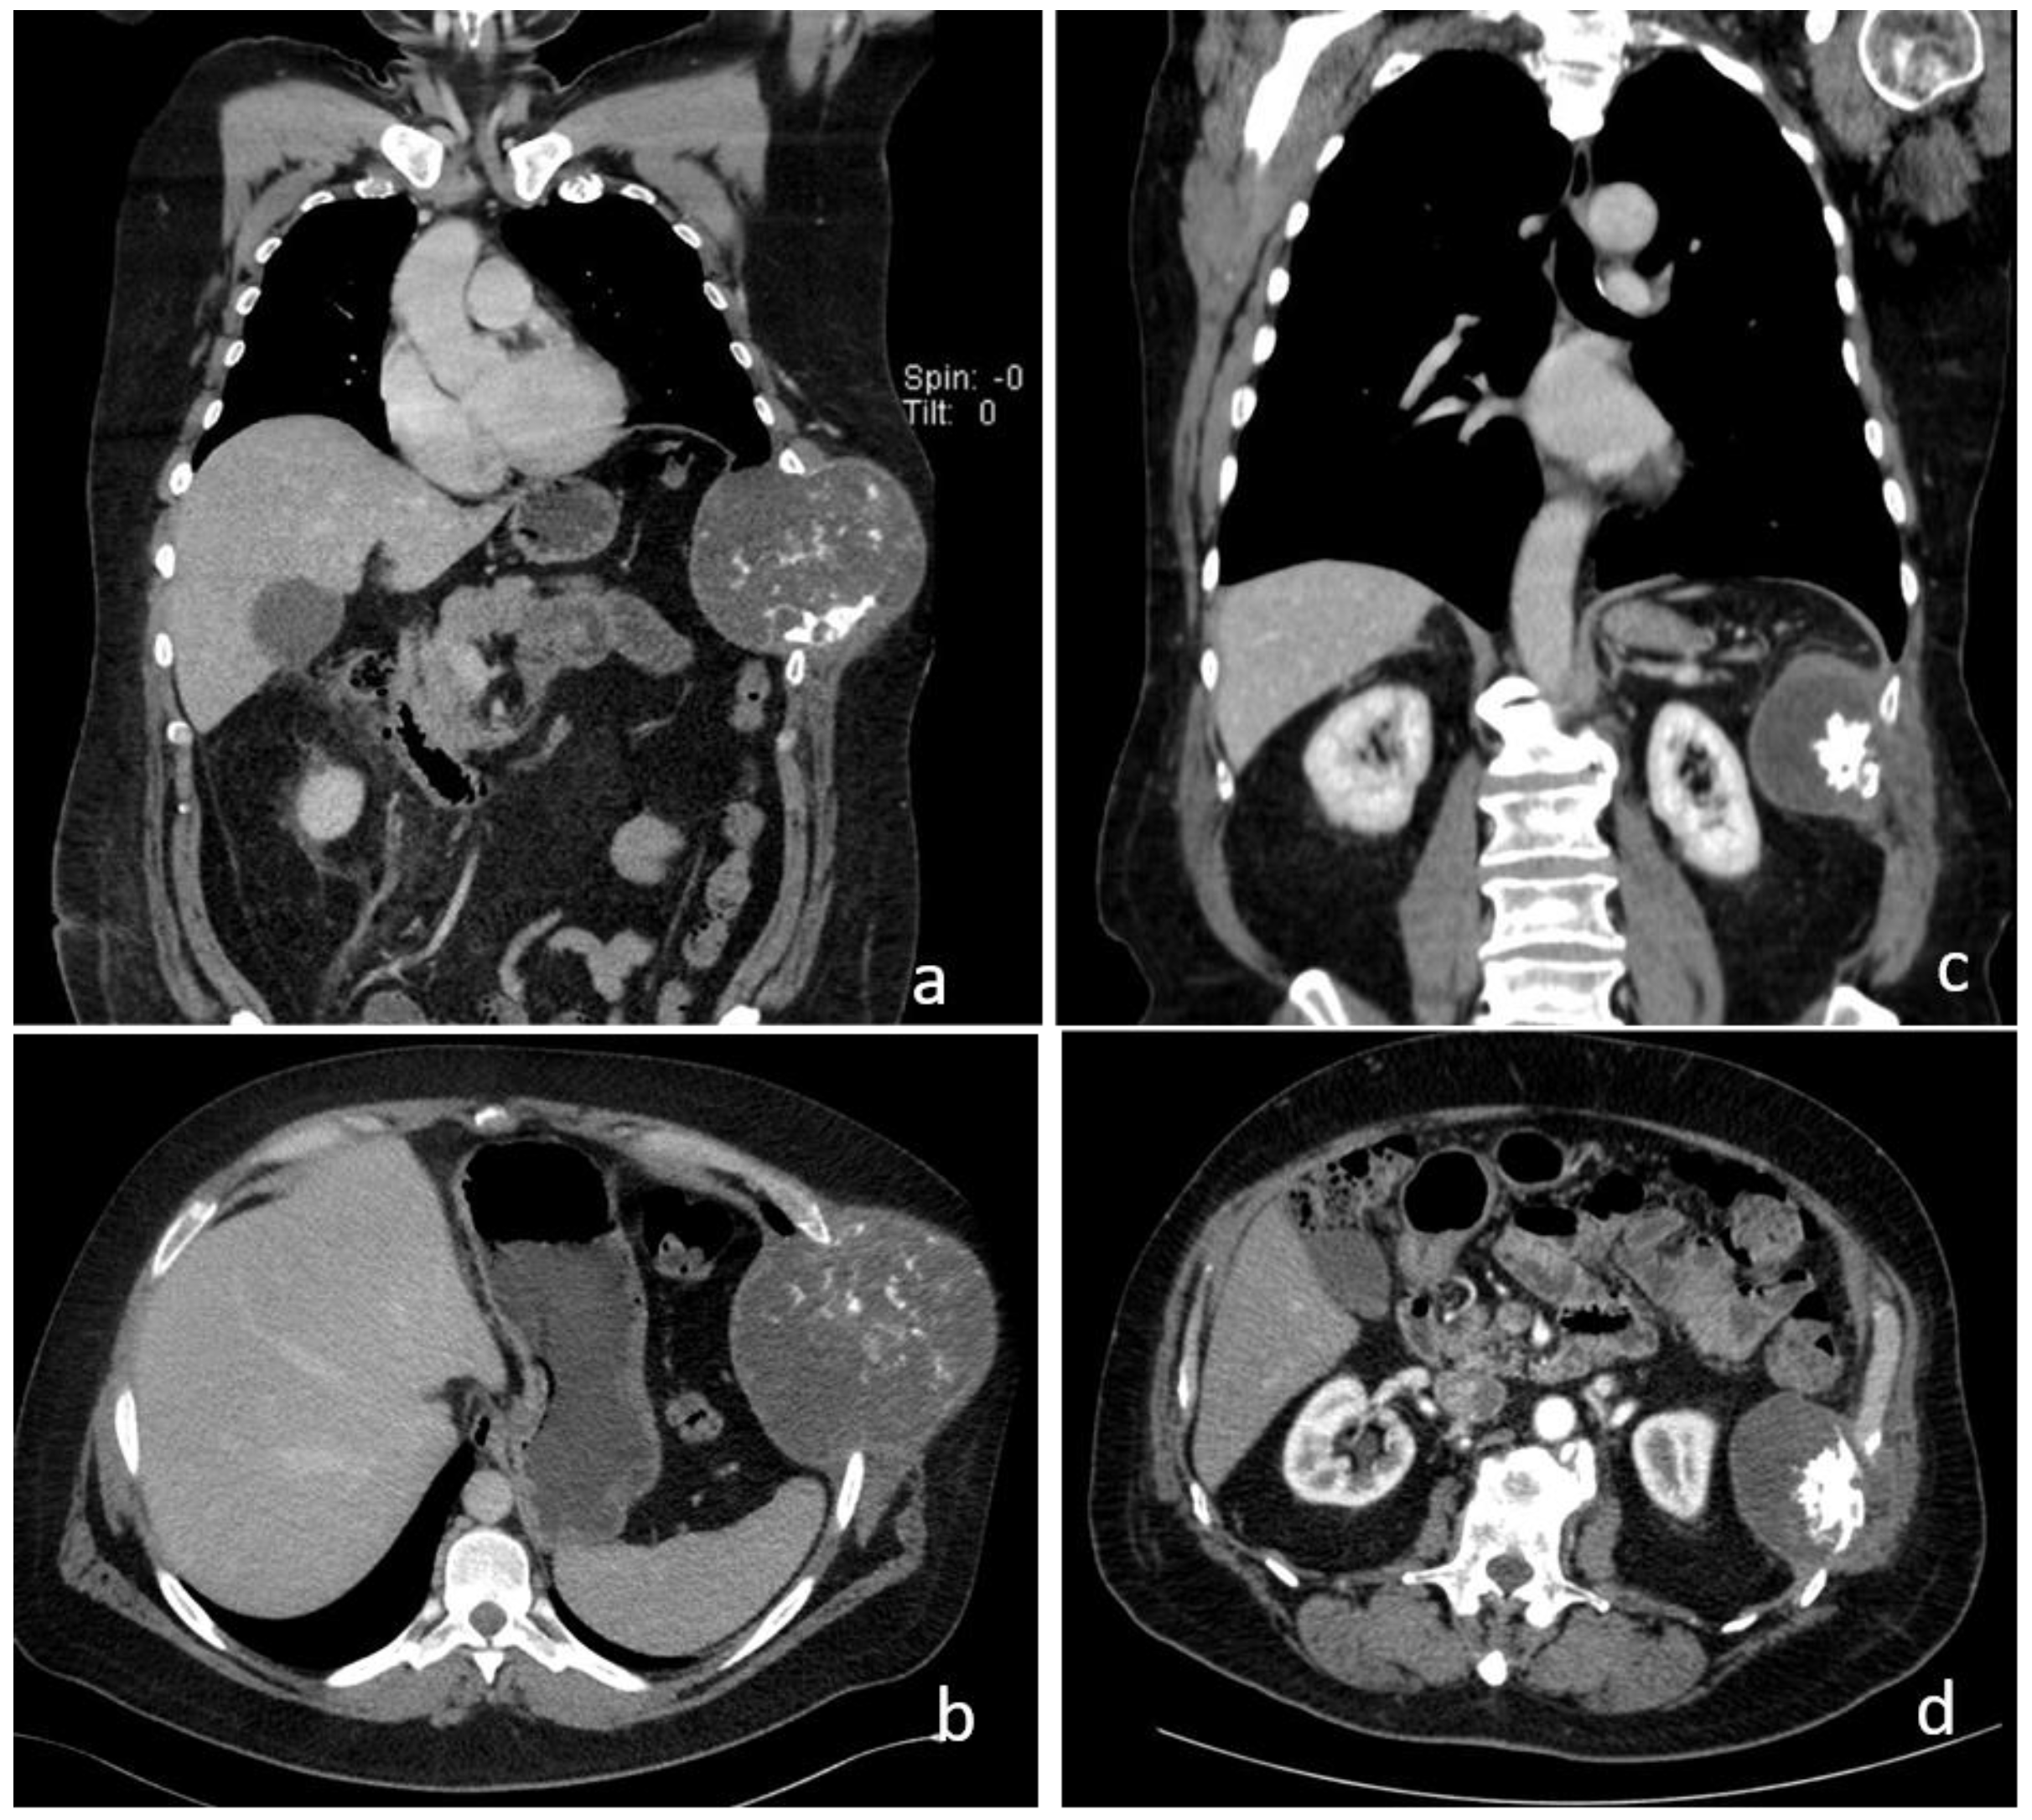

Figure 1.

Computed tomography findings of two patients with primary chondrosarcoma of the chest wall in coronal (a,c) and axial reconstruction (b,d). Tumor involving the 7th and 8th ribs (a,b). Tumor involving the 9th and 10th ribs (c,d).